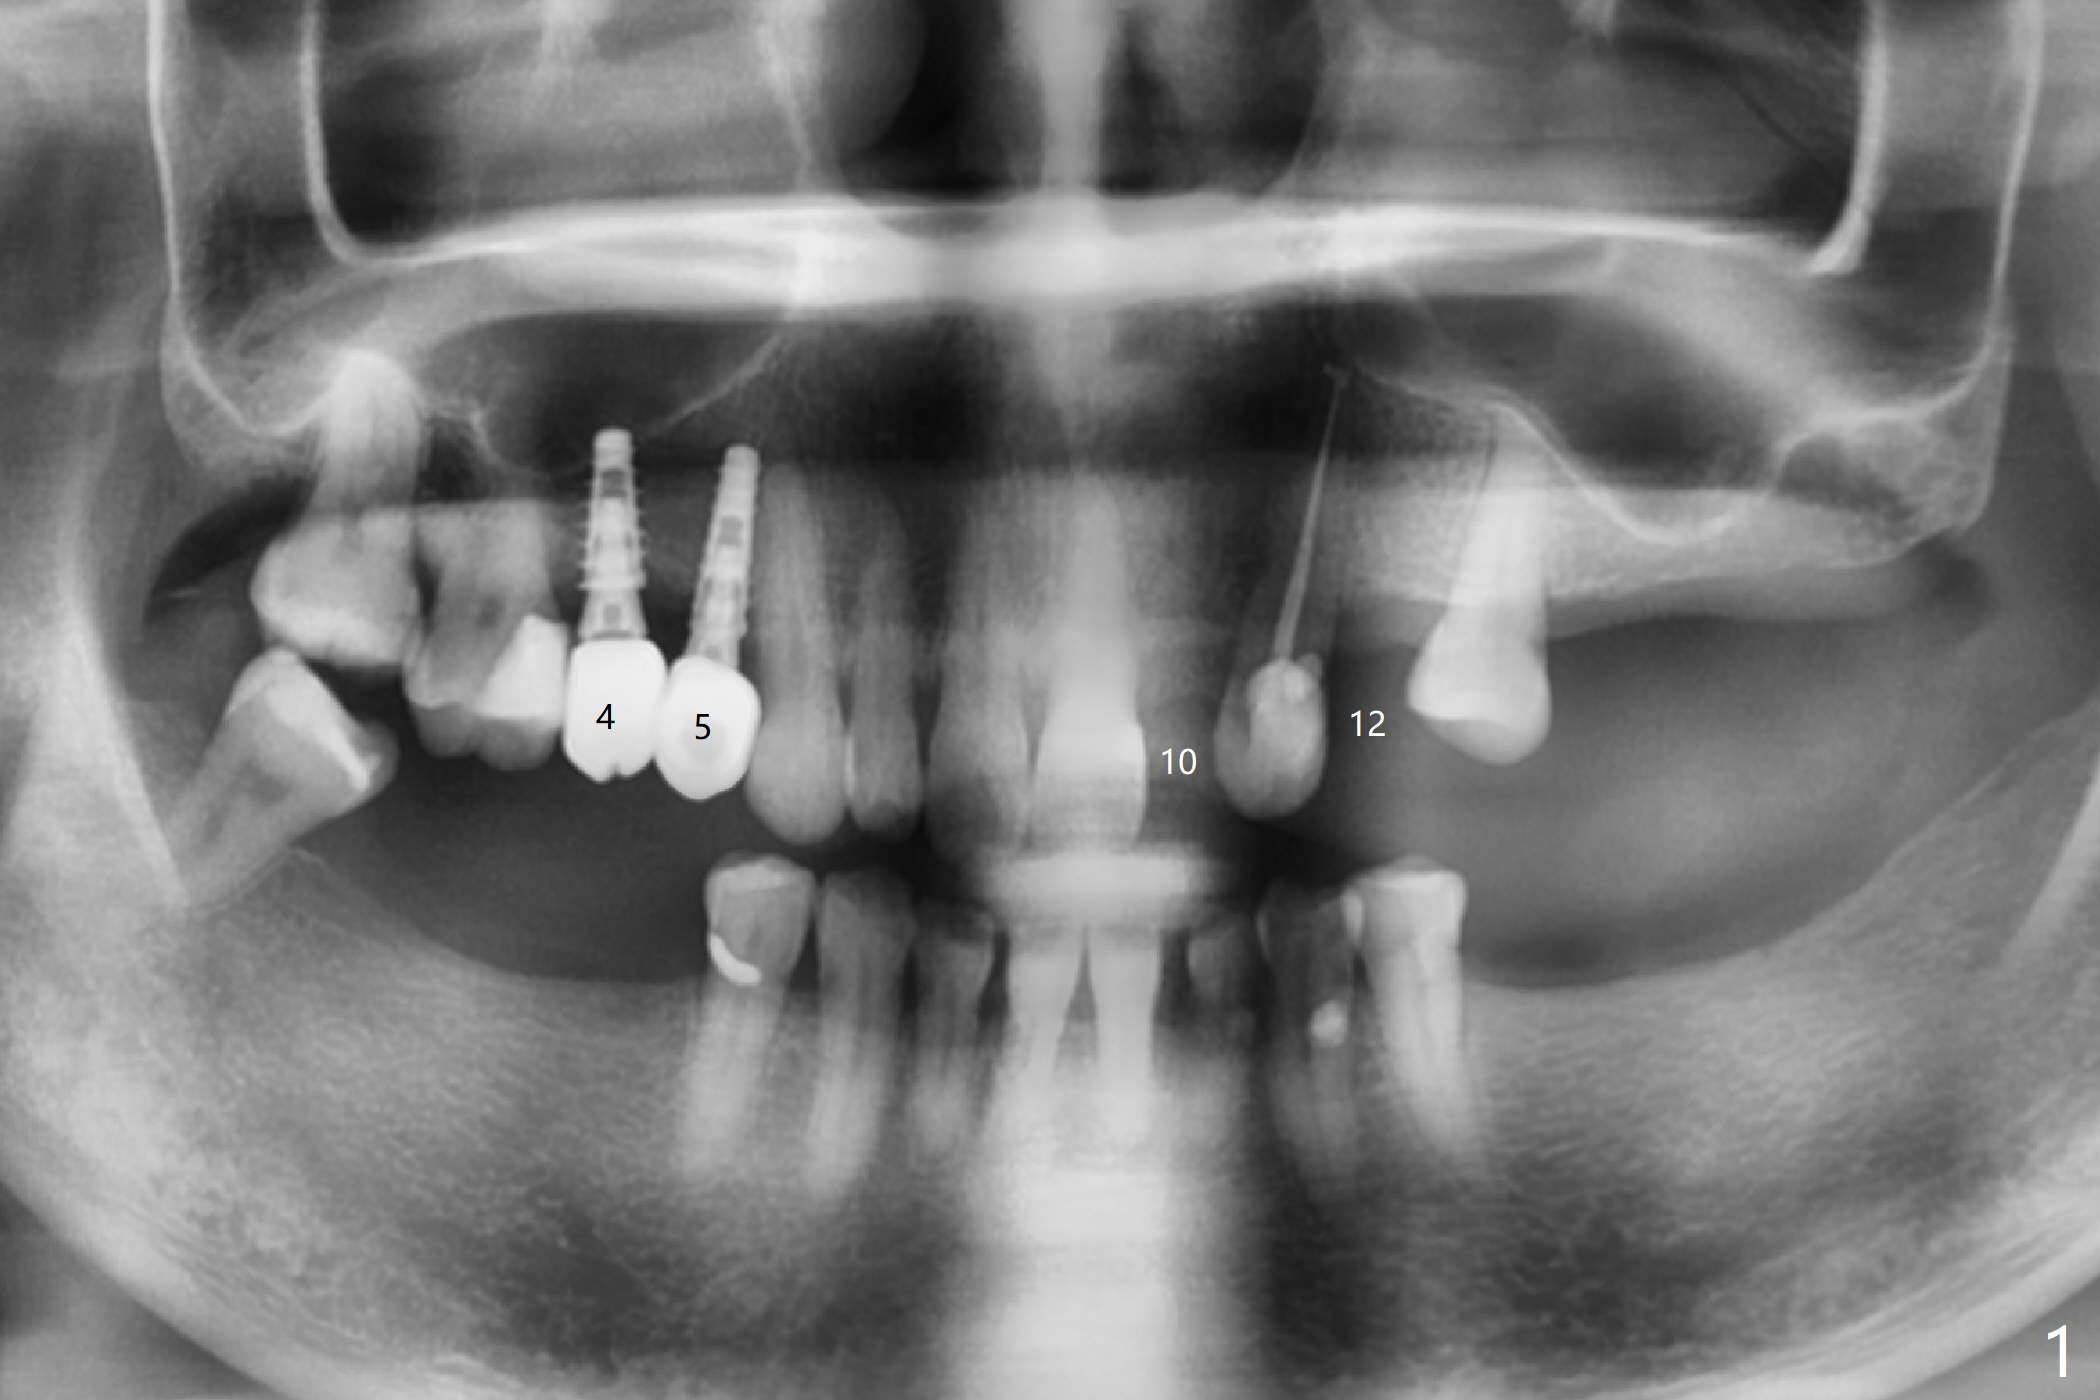

I looked at #10 site and I see that bone width is way too narrow to place 3.5mm implant (Fig.4). Jennifer

In fact, I want to place a 2 or 2.5x10-13 mm 1-piece implant.  Can you modify the protocol so that I can use pointed drill and possibly 2.2 mm one as long as possible without tissue punch or bone trimmer?  Help me go over the narrowest portion of the bone.  Then I use free hand technique.  Please help me as much as possible.  If it is difficult, can you ask your boss to modify the kit and work on the 1-piece implant?  I really hate to do this case, but the patient's flipper has been repaired several times.  Thanks.